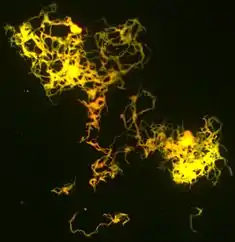

Mycobacterium tuberculosis (M. tb), also known as Koch's bacillus, is a species of pathogenic bacteria in the family Mycobacteriaceae and the causative agent of tuberculosis.[1][2] First discovered in 1882 by Robert Koch, M. tuberculosis has an unusual, waxy coating on its cell surface primarily due to the presence of mycolic acid. This coating makes the cells impervious to Gram staining, and as a result, M. tuberculosis can appear weakly Gram-positive.[3] Acid-fast stains such as Ziehl–Neelsen, or fluorescent stains such as auramine are used instead to identify M. tuberculosis with a microscope. The physiology of M. tuberculosis is highly aerobic and requires high levels of oxygen. Primarily a pathogen of the mammalian respiratory system, it infects the lungs. The most frequently used diagnostic methods for tuberculosis are the tuberculin skin test, acid-fast stain, culture, and polymerase chain reaction.[2][4]

Other bacteria are commonly identified with a microscope by staining them with Gram stain. However, the mycolic acid in the cell wall of M. tuberculosis does not absorb the stain. Instead, acid-fast stains such as Ziehl–Neelsen stain, or fluorescent stains such as auramine are used.[4] Cells are curved rod-shaped and are often seen wrapped together, due to the presence of fatty acids in the cell wall that stick together.[12] This appearance is referred to as cording, like strands of cord that make up a rope.[9] M. tuberculosis is characterized in tissue by caseating granulomas containing Langhans giant cells, which have a "horseshoe" pattern of nuclei.